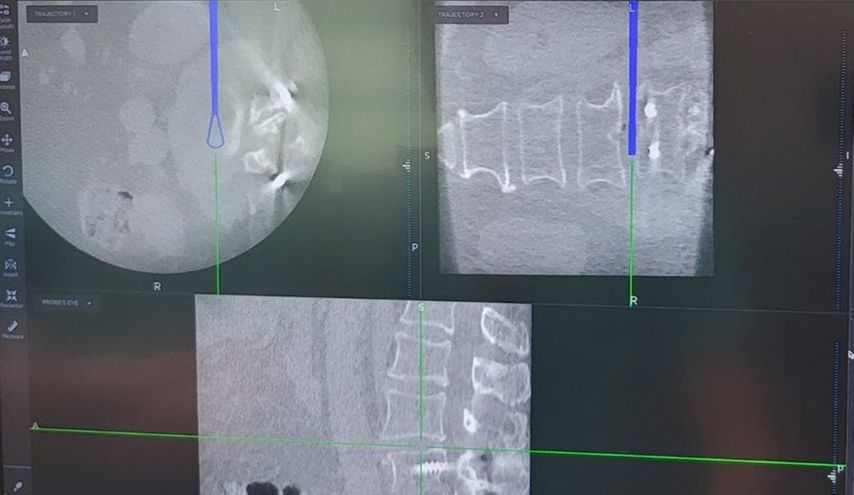

Beispiel für die Implantation zervikaler Pedikelschrauben. In diesem Fall kam es bei einem 61-jährigen Patienten 10 Jahre nach anteriorer zervikaler Diskektomie und Fusion (ACDF) C4/5 und ventraler Verplattung C4–6 zu einer Ankylosierung auch von C6/7. Nach Sturz kam es zu einer Fraktur bei C6/7 mit begleitender Bogenfraktur und auch Beteiligung der dorsalen Ligamenta (Abb. 1 und 2). Klinisch bestanden ausgeprägte Nackenschmerzen und kein neurologisches Defizit. Es wurde die Indikation der dorsalen Verschraubung von C4 auf Th1 gestellt. Intraoperativ wurde routinemäßig zusätzlich eine kleine Referenzschraube in einer Lamina – entfernt von der Dornfortsatz-Referenzklemme für die Navigation – gesetzt. Mit dieser konnte intraoperativ die Genauigkeit der Navigation exakt überprüft werden (Abb. 4 und 5). Mittels navigierter High-Speed-Fräse wurden die Schraubenkanäle vorgebohrt (Abb. 6), im Anschluss wurde der Bohrkanal ausgetastet und die Schrauben wurden implantiert. Abbildung 7 zeigt eine Röntgenkontrolle 3 Monate postoperativ.

Abb. 4: Screenshot der Navigationssoftware intraoperativ (Stealth Station S7). Es erfolgt die intraoperative Verifizierung der Navigationsgenauigkeit mittels kleiner Schraube in der Lamina, positioniert idealerweise entfernt von der Dornfortsatz-Referenzklemme. Die navigierte Fräse wird im Situs exakt auf die Schraubenmitte gerichtet, und die Navigation bestätigt die Genauigkeit | |